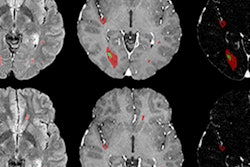

The Pixyl team delivered both the fastest and most accurate predictions of two-year clinical disability from MRI scans of a patient with multiple sclerosis (MS), according to the company.

Pixyl believes that MR image analysis is an important step toward assessing and predicting clinical disability in MS and, thus, personalizing treatment for patients.